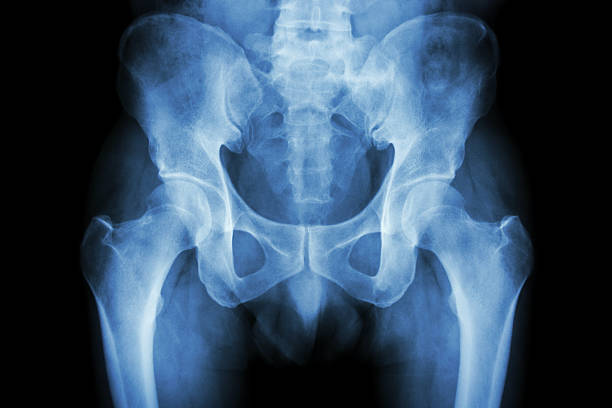

고관절 충돌 증후군은 엉덩이 통증의 주요한 원인 중 하나입니다. 이 질환은 골반 뼈와 대퇴골 사이에서 발생하는 충돌에 의해 2 관절 사이의 연골이 손상되는 질환입니다. 고관절의 구조적인 문제나 잘못된 자세, 과도한 스트레칭 등으로 발생할 수 있습니다.

천장관절은 척추에 충격을 흡수하고 체중 부하를 받아주는 관절로, 다양한 원인으로 인해 손상이 생길 수 있습니다. 특히 여성의 임신 및 출산 후 호르몬 변화로 인해 발생하기도 합니다. 이런 경우에도 엉덩이 통증이 나타날 수 있으며, 고관절 충돌 증후군과 증상이 유사하여 헷갈릴 수 있습니다.

관절염

엉덩이 관절의 염증이나 변형으로 인해 엉덩이 통증이 발생할 수 있습니다. 나이가 들어가면서 관절염이 악화되어 엉덩이 통증이 생기는 경우가 많습니다. 이러한 경우에는 전문의의 치료와 적절한 관리가 필요합니다.